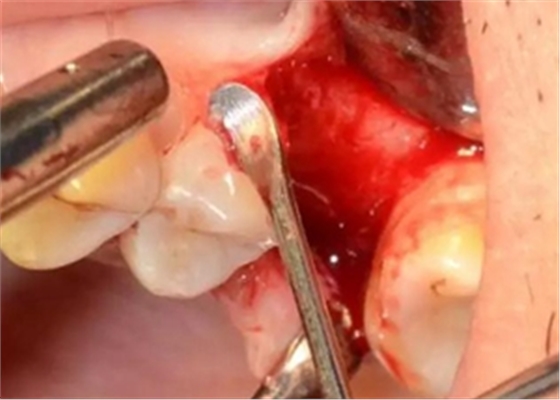

局麻后切開翻瓣

暴露骨面,輕柔處理軟組織

清理骨面和臨牙齦下結(jié)石及炎性肉芽組織